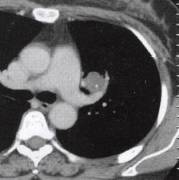

肝癌肺转移(3)肺部其他恶性肿瘤如肺原发肉瘤、肺癌肉瘤等。常症状轻微甚至无症状就诊时间 较晚,X线及CT表现为圆形、椭圆形肿块,边缘光滑,分叶多不明显,可为小切迹样或铸 型表现,直径多达6〜7cm,大者可占据一叶肺甚至一侧胸腔(图4)。增强肿块呈不规则

明显强化,表面常有包膜或假包膜。极少有肺门纵隔淋巴结转移。 医学百科网 | YxBaike.Com